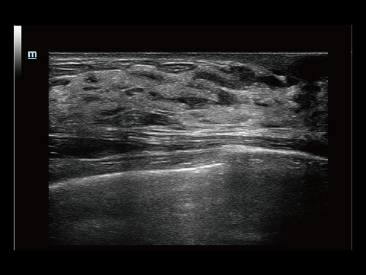

Resona 7

Mindray? ??? ??? ?? ??? ???? ??? ?? ??? ??? ????? ??? ????. ?? ???? ZONE Sonography? ??? ???? ?? Resona 7? ??? ZST+ ???? ?? ?? ? ?? ??? ????? ?? ??? ??? ??? ? ?? ????.

?? Resona 7? ???? ??? ?? ???? ??? ??? ???? ??? ?? ???? V Flow? ?? CNS ??? ?? 3D ??? ???? ?? ???? ?? ??? ?? ?? ?? ??? ??????. ???? ??? ??? ?? ?? ??? ??? ?? ?? ??? ??? Resona 7? ??? ???? ???? ??? ??? ??? ????.